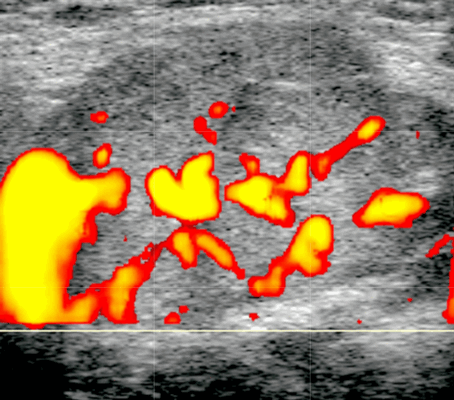

Цветной допплер. Повышенная паренхиматозная васкуляризация при синдроме Шегрена и коррелирует с тяжестью заболевания

- Острый калькулезный сиаладенит (ОКС). Односторонняя, увеличенная, гипоэхогенная, гетерогенная поднижнечелюстная железа (ПЧЖ). Расширение интра- / внегландулярных протоков и слюнной камень. Болезненность при давлении датчиком, нет явного повышения васкуляризации при ЦДК

Лучший диагностический признак. Острый: одностороннее увеличение, гипоэхогенная структура поднижнечелюстной железы на УЗИ, повышенная васкуляризация при ЦДК ± расширение протока ± слюнной камень. Хронический: одностороннее атрофическое поражение, гипоэхогенная структура, гетерогенные зоны, гиповаскулярный ± расширение протоков ± слюнной камень

Бескаменный сиаладенит. Одностороннее увеличение гипоэхогенной слюнной железы. Нет расширения протока или камней. Болезненность при давлении датчиком. Повышенная внутрижелезистая васкуляризация